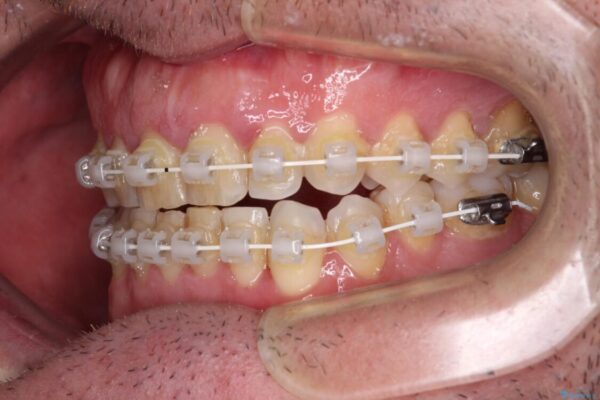

治療途中

• 前歯でものを噛みきりたい 目立たない装置でのワイヤー矯正 治療途中画像

以前矯正治療を経験されたそうですが、舌の突出癖により上下前歯に隙間ができている様子でした。

前歯の非接触改善は、インビザラインの得意とするところですが、マウスピース矯正は絶対に継続できないとのことで、ワイヤー装置にて矯正治療を行うこととしました。

舌の突出癖が改善されない限り、非接触改善は見込めないため、トレーニングを徹底するように指示しました。